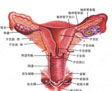

盆腔器官脱垂(POP)

疾病介绍:指盆腔器官脱出于阴道内或阴道外。阴道前壁脱垂也即阴道前壁膨出,阴道内2/3膀胱区域脱出称之膀胱膨出。若支持尿道的膀胱宫颈筋膜受损严重,尿道紧连…【详细】